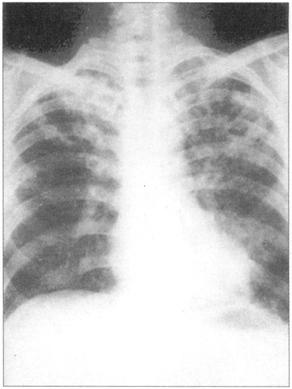

①周围性发绀及周围静脉扩张是由COPD引起的CO2潴留的主要特征(图76)。②脊柱侧后凸常预示患者有某种呼吸系统疾病的倾向(图77)。③结核的X线表现(图78)。④肺尖部结核所致的纤维化多引起上胸部变平(图79),由于脊柱常受累,故多有成角。⑤支气管肺癌(图80)。⑥大叶肺炎患者常伴发单纯疱疹病毒感染(图81、图82)。⑦如肺组织萎陷(如气胸),则胸片上无法看到肺纹理(图83)。

图78 结核,在肺上叶可见空洞